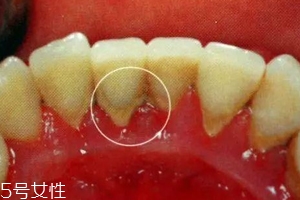

牙結(jié)石是不會自動脫落的,因為它牢牢的附著在牙齒表面,當(dāng)然有時候會有極少數(shù)的牙結(jié)石會因為你刷牙或者用牙簽剝落,只是極少數(shù)現(xiàn)象。所以有了牙結(jié)石千萬不能忽視,它不會像感冒一樣會自行康復(fù)的,它們只會在你的牙齒表面沉積下來,日積月累,使你的口腔患上炎癥,這樣只會導(dǎo)致牙齦炎癥逐漸加重,并發(fā)展為牙周炎,最終導(dǎo)致牙齒松動脫落。不要奢求牙結(jié)石會自動脫落了,請重視起來,為了你有一口健康的好牙!

牙結(jié)石的三個階段

牙結(jié)石第一階段:我們口腔并不是無菌的狀態(tài),口腔內(nèi)有無數(shù)個細(xì)菌,每當(dāng)我們吃飯食物,食物殘渣在口腔縫隙超過5分鐘之后就會形成牙菌斑(牙菌斑就是牙結(jié)石的幼年體)。而且,牙菌斑是粘附在牙齒表面的不易被沖走,這就給更多的細(xì)菌提供肥沃的土壤,一般來說,牙菌斑會在1-2h迅速增厚,10天之內(nèi)發(fā)展成熟達(dá)到高峰,所以我們應(yīng)當(dāng)在12h左右清除牙菌斑(牙刷,牙線)。

牙結(jié)石第二階段:細(xì)菌有了肥沃的土壤,便會呼朋喚友前來定居,這時候,如果你還不注意口腔衛(wèi)生,不及時清除食物殘渣,那么,牙菌斑和食物殘渣會在「唾液」的侵泡下經(jīng)過24小時會被唾液中的成分「鈣化」,變成「初始」的牙結(jié)石啦。

牙結(jié)石第三階段:然而,牙結(jié)石并不是一成不變的,這種初始的牙結(jié)石會繼續(xù)沉積、礦化,越積越后,越積越硬,最后牙刷都拿它沒辦法,只能通過醫(yī)用器械將其清除。